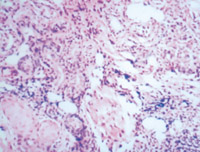

5-2-4 傷后第5天,真皮淺層組織液化性壞死、剝落  HE×100